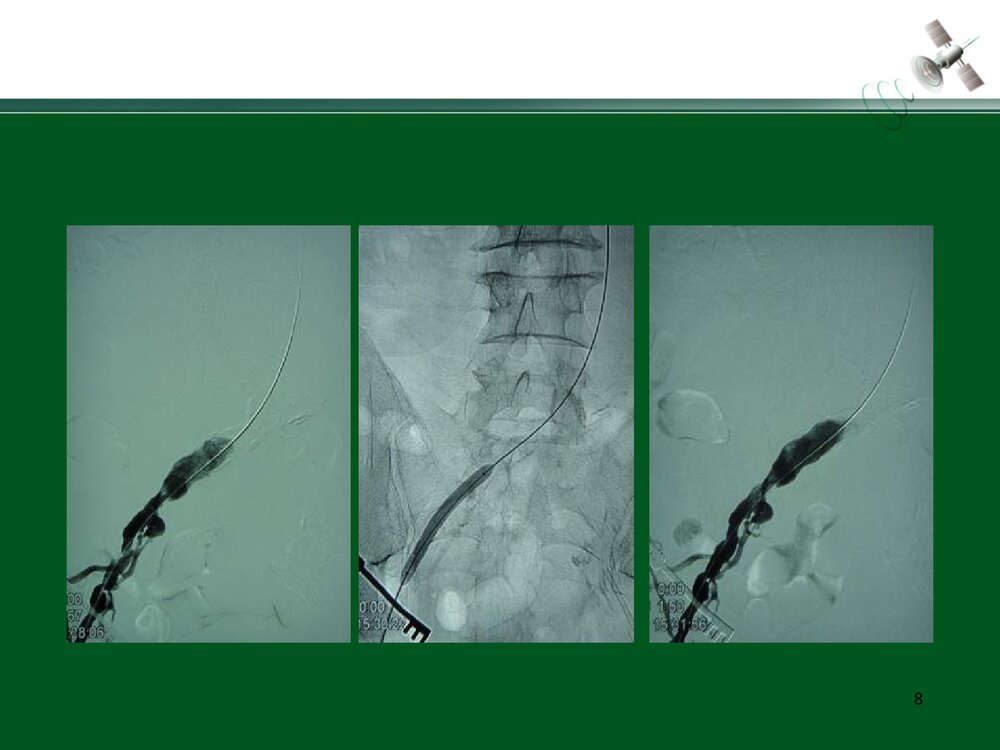

复杂腹主动脉瘤的腔内治疗常光其王深明教育部国家重点学科卫计委国家临床重点专科中山大学附属第一医院血管外科中山大学血管外科研究中心1复杂瘤颈AAA的腔内治疗复杂瘤颈指下列情况1.瘤颈长度小于15mm;2.瘤颈角度大于60度;3.瘤颈直径过大或过小(小于18mm或大于32mm)例1:短瘤颈AAA的EVAR3456例2:短瘤颈伴入路血管狭窄AAA的EVAR7891011例3:瘤颈狭窄且成角大于60度AAA的EVAR12131415161718192021例4:瘤颈成角大于60度AAA的EVAR2223242526例5:瘤颈成角伴腹主动脉分叉狭窄AAA的EVAR272829303132复杂入路AAA的腔内治疗复杂入路是指下列情况:(1)髂动脉弯曲成角超过90°;(2)双侧髂股动脉广泛钙化伴严重狭窄,直径小于7mm;(3)双侧髂股动脉闭塞例6:入路血管严重狭窄AAA的EVAR34353637383940例7:入路血管严重...